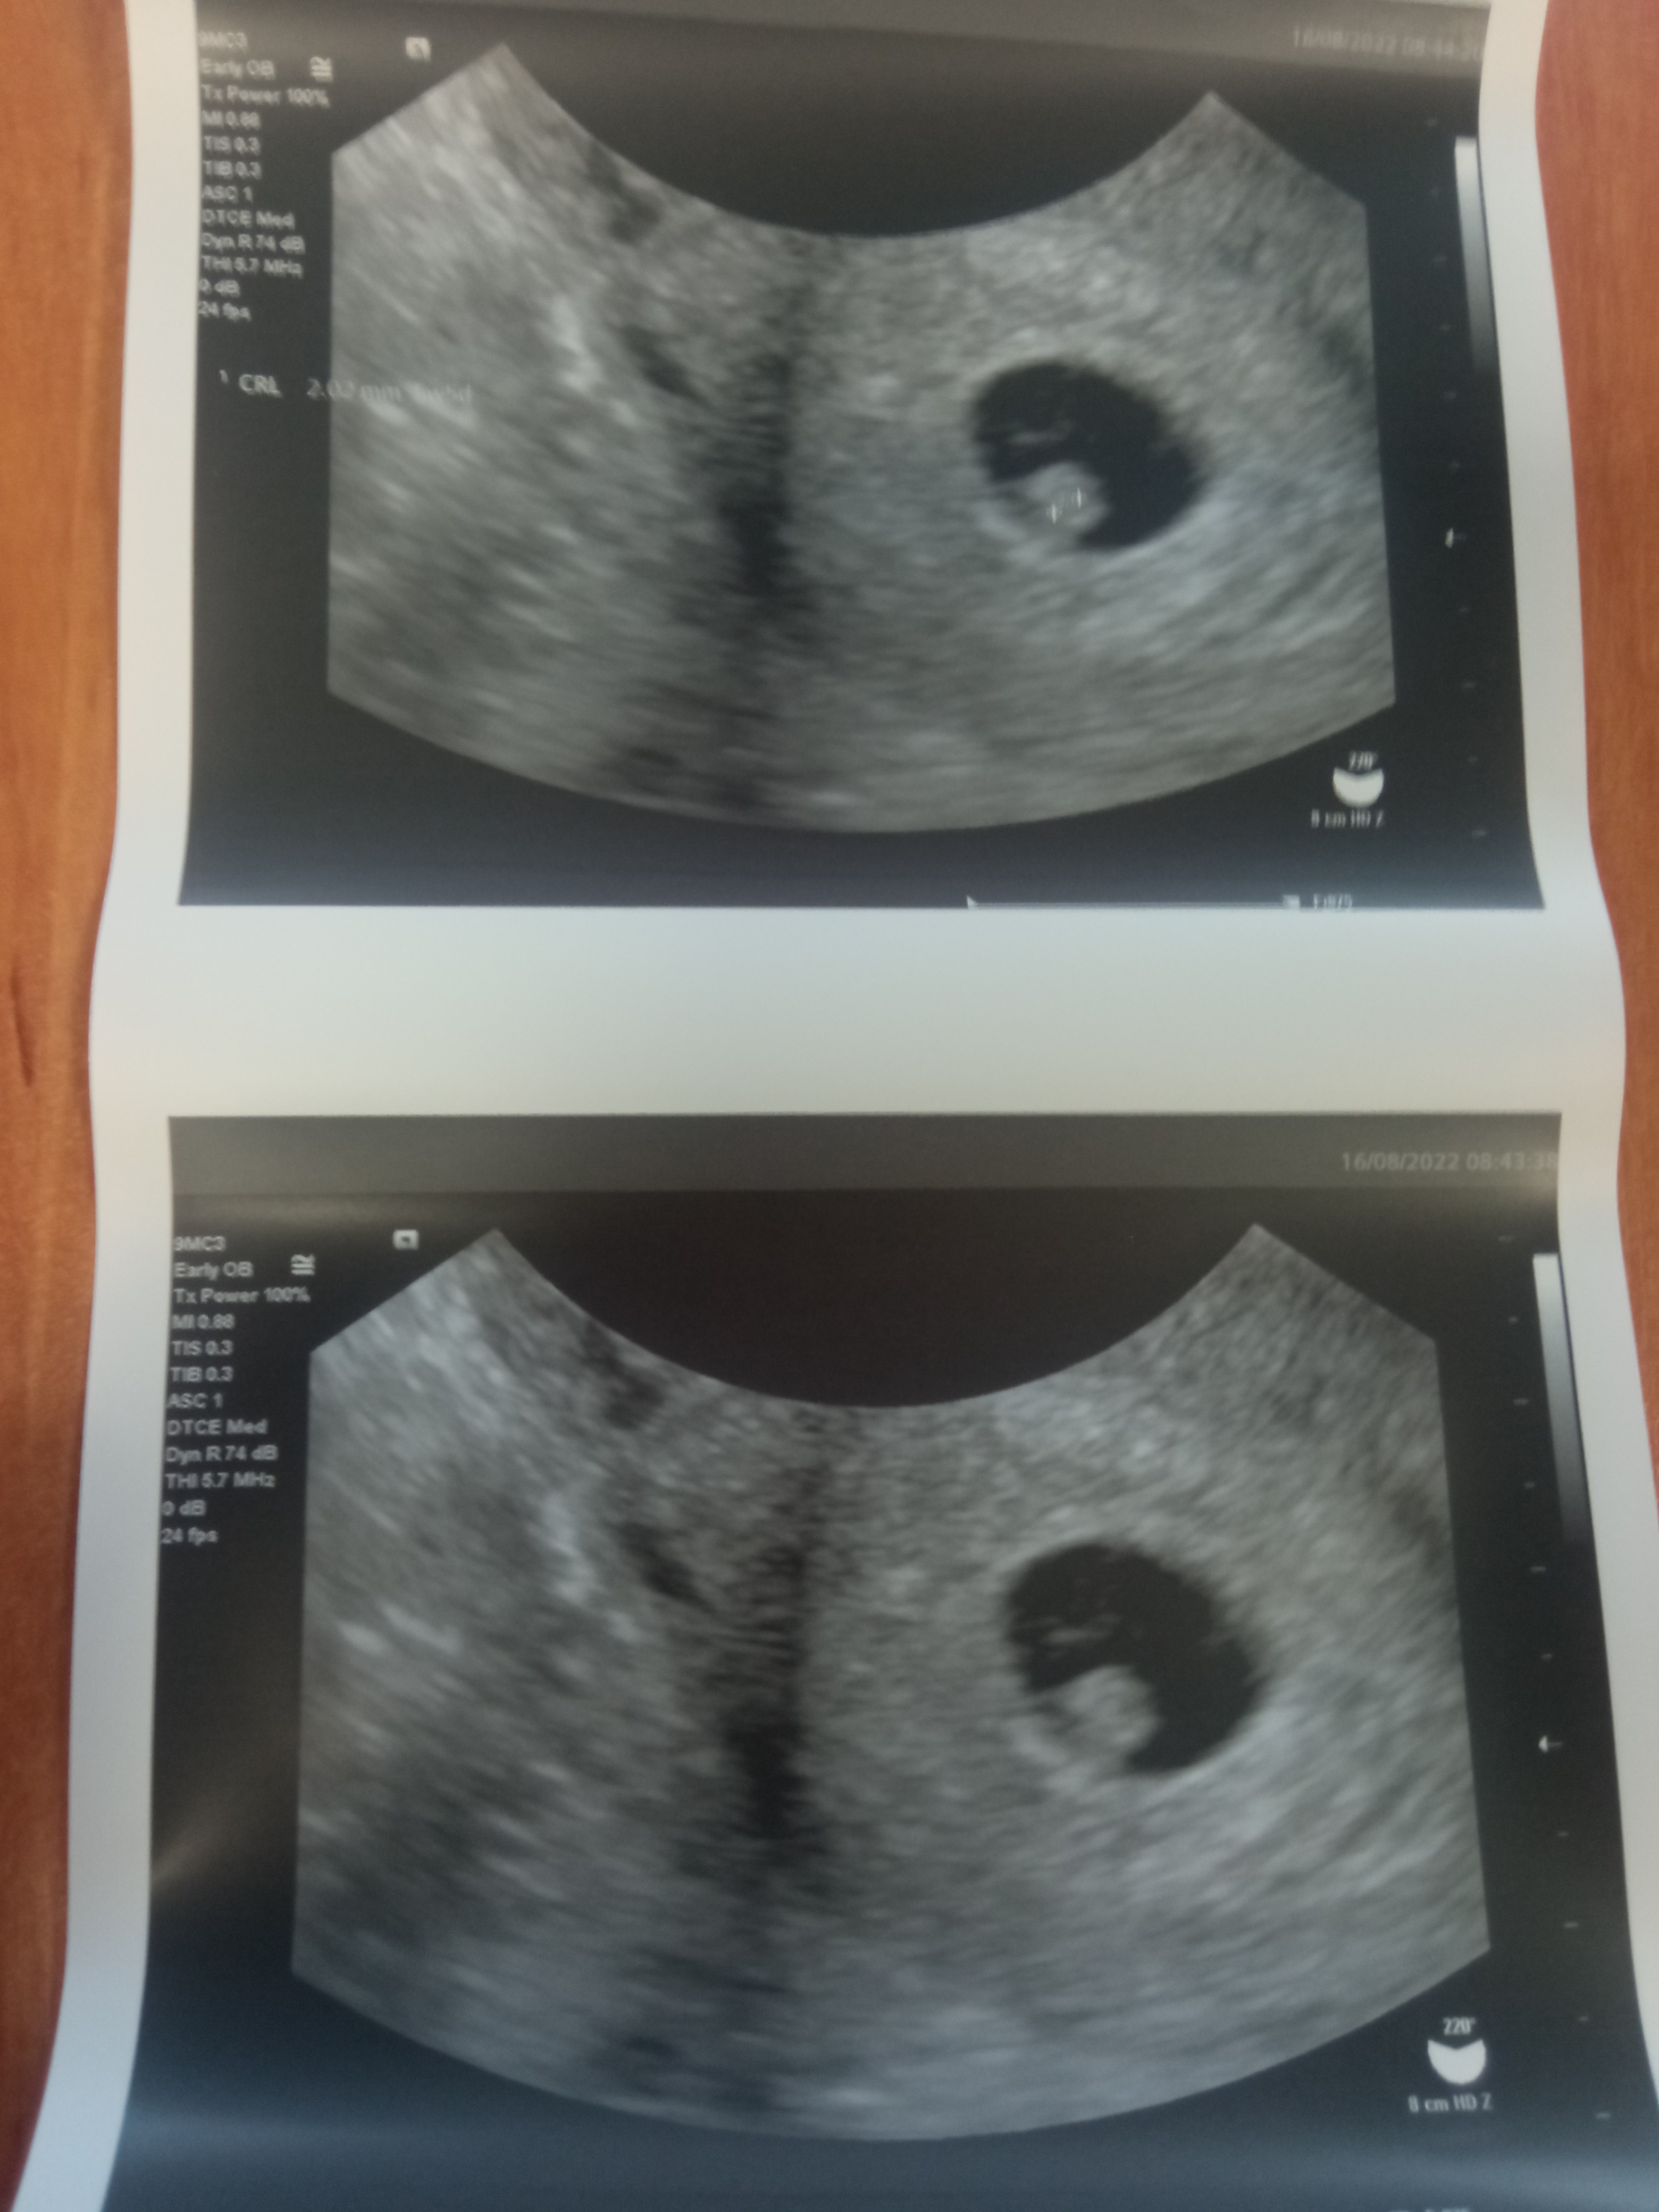

Witam się po pierwszym USG w 7t+2d. Narazie bez słuchania serduszka ale lekarz mówił że pulsuje :) z USG 5t. Następna wizyta za miesiąc 😱

Załączniki

• IMG_20220816_084914.jpg

IMG_20220816_084914.jpg

1,4 MB · Wyświetleń: 114